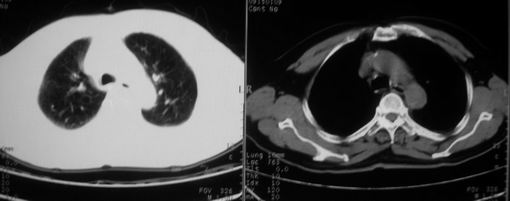

ct左肺下叶大片状高密度影,病变密度不均,界限不清,左侧胸腔积液,治疗后复查临床症状好转而影像学表现病变有发展,还是首先考虑感染性病变,复查时间短附合感染性病变的病理改变。

两肺炎症感染(以左肺下叶为著),双侧少量胸腔积液;建议继续抗炎治疗。